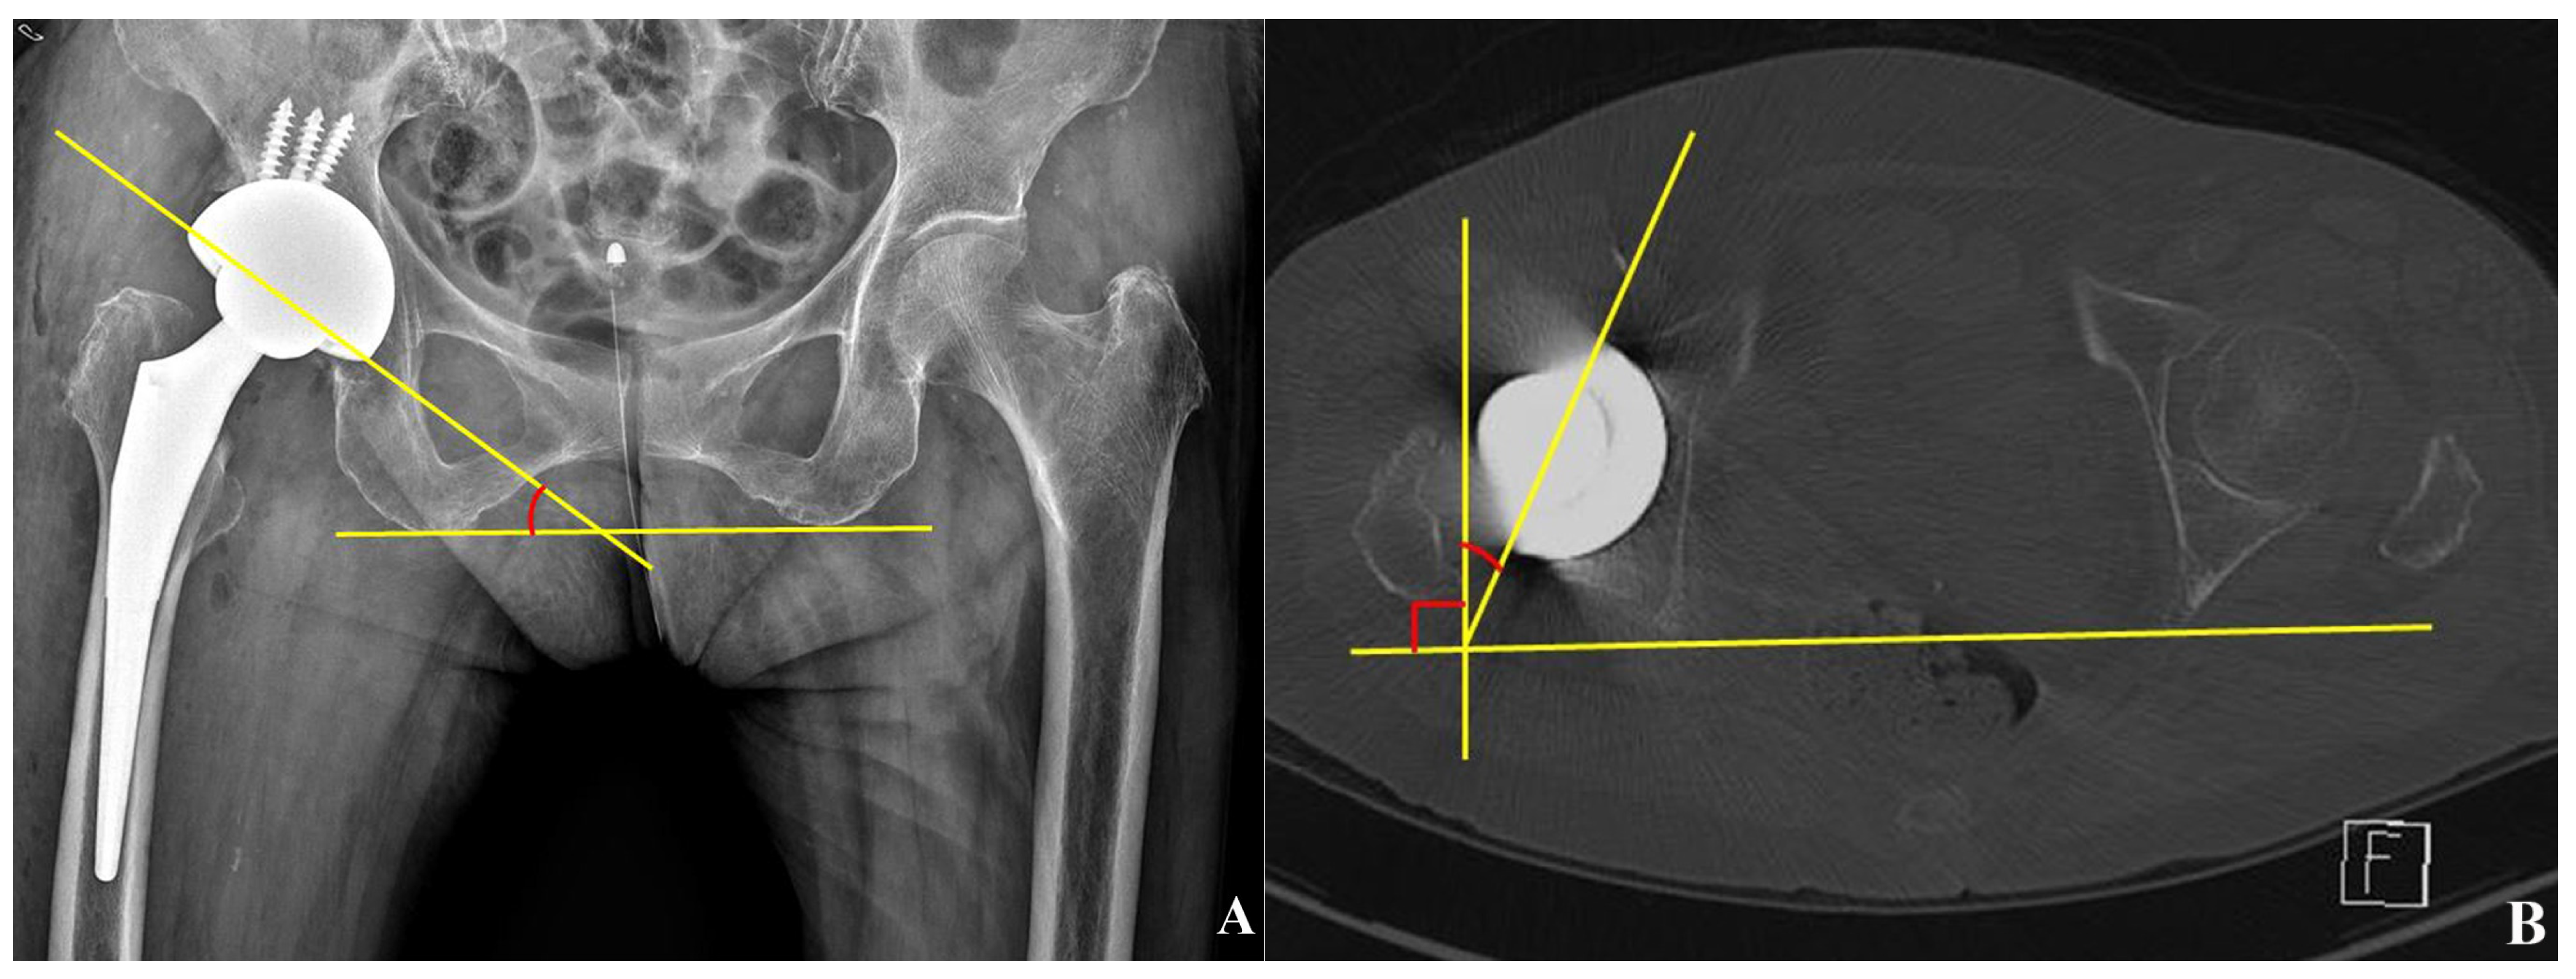

2.4. Cup Position and Fixation

2.5. 2D-Based Measurement of Host Bone Coverage from Plain Radiographs of the Pelvis

2.6. 3D-Based Measurement of Host Bone Coverage from CT Scans